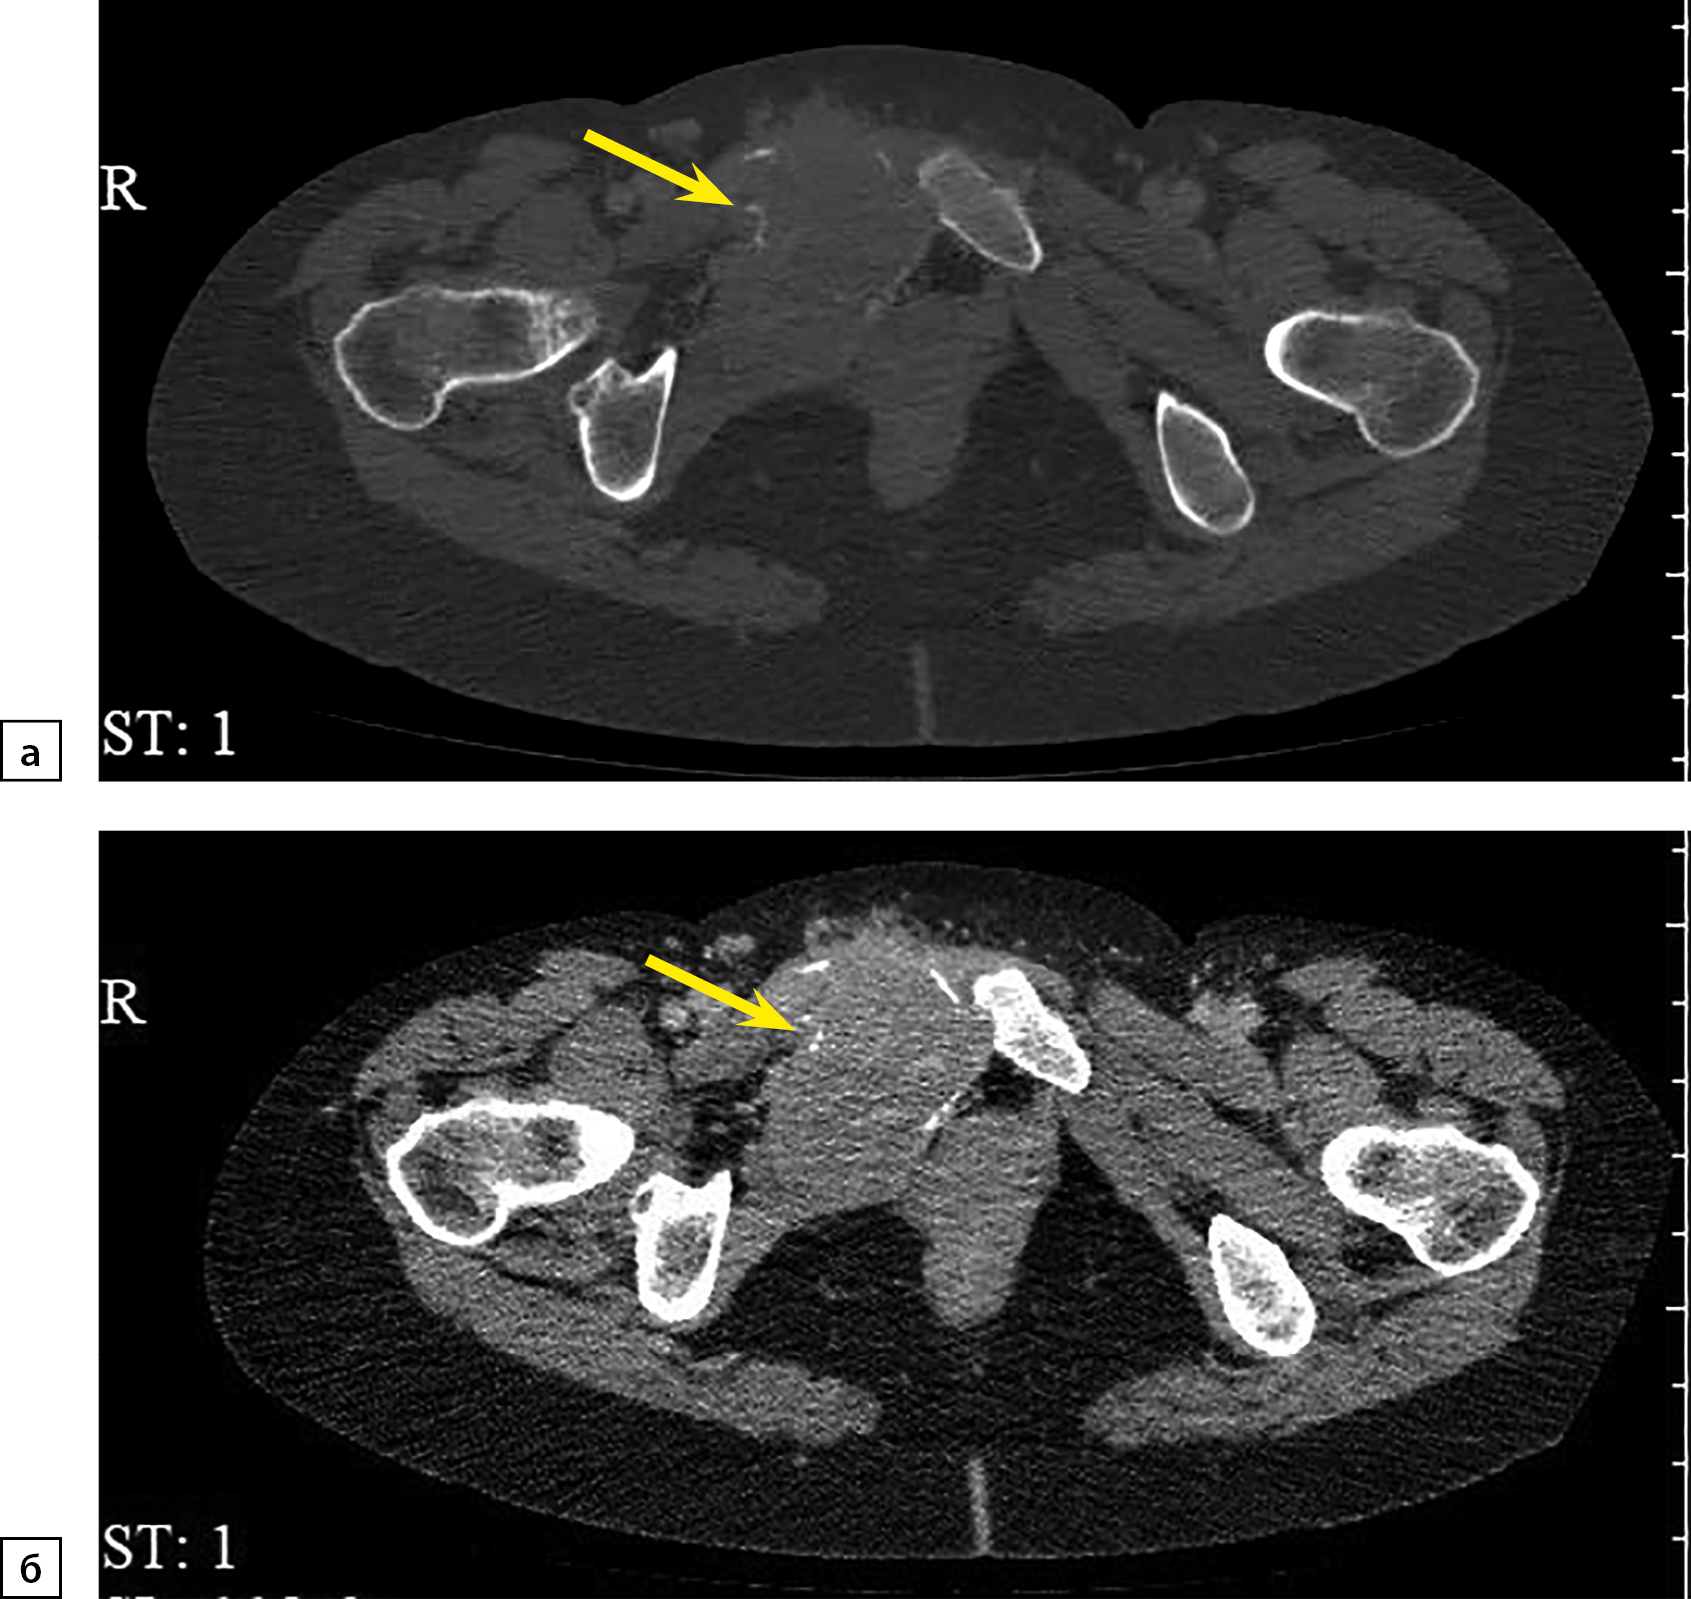

При повторной КТ органов шеи, грудной клетки, брюшной полости и малого таза с болюсным контрастным усилением: КТ-признаков патологических образований органов грудной клетки и шеи не выявлено, визуализируется участок разрежения костной ткани рукоятки грудины, без четких контуров, патологических образований переднего средостения не выявлено, желчный пузырь в размерах не увеличен, в просвете — рентгенконтрастные конкременты до 6 мм в диаметре и плотностью +700 HU. Левый надпочечник увеличен за счет многоузлового образования размерами 110х90х150 мм, плотностью +30 HU. В I фазу накопление контрастного вещества до +60 HU, во II фазу — до +60 HU, через 10 минут плотность образования +50 HU. Правый надпочечник увеличен за счет многоузлового образования размерами 120х120х200 мм, плотностью +30 HU. В I фазу накопление контрастного вещества — до +80 HU, во II фазу — до +75 HU, через 10 минут плотность образования +50 HU. Структура образований обоих надпочечников неоднородная за счет многочисленных зон некроза в центре. Образования обильно васкуляризированы. Надпочечниковые вены широкие, до 10 мм в диаметре (рис. 1). Данных за инвазию окружающих структур, сосудов не получено. Данных за тромбоз нижней полой вены не получено. Лимфатические узлы не увеличены. Очаг остеолитической деструкции в правой лонной кости с наличием мягкотканного компонента размерами 50х40х40 мм (рис. 2).

Рисунок 1. Компьютерная томография органов брюшной полости с контрастированием: а — артериальная фаза, коронарная плоскость; б — венозная фаза, аксиальная плоскость; в — артериальная фаза, сагиттальная плоскость. Стрелками отмечены гигантские множественные феохромоцитомы обоих надпочечников.